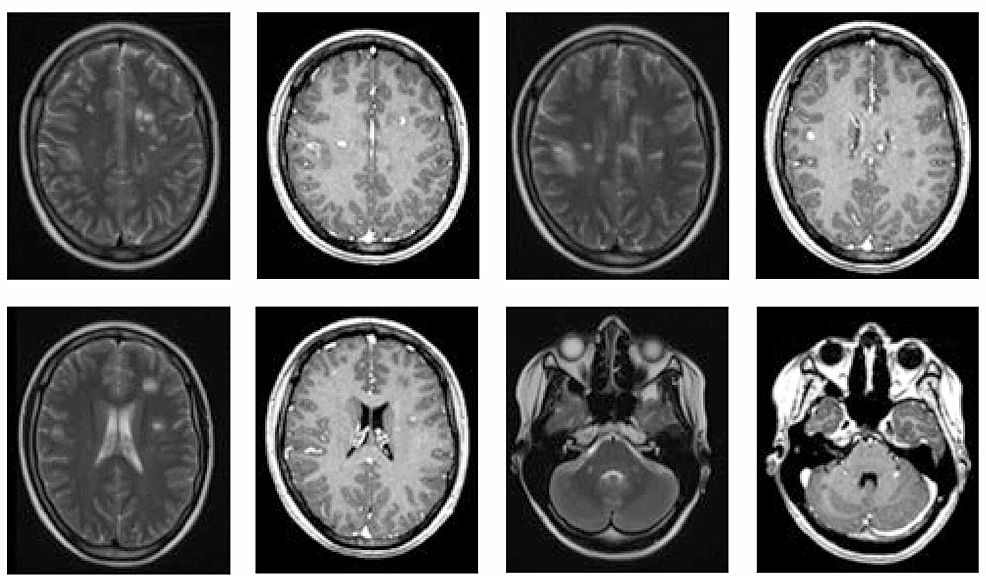

Collection of Brain Disease Stock Photo

Collection of Brain Disease Stock Photo Image of care, cerebral 65493484